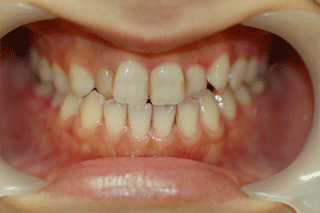

ひどい虫歯(C4)

C4 歯根のみ 初期において無症状だが、ばい菌が歯の神経のあった管を通じて生体に及ぶと、歯の根の先の部分が腫れたり、膿がでてきたりする。 初期、神経のあった管をきれいにして、管を密閉させる薬材をいれる。

その後、歯を補強(支台築造)し補綴処置(かぶせ物)をする。

末期、抜歯。